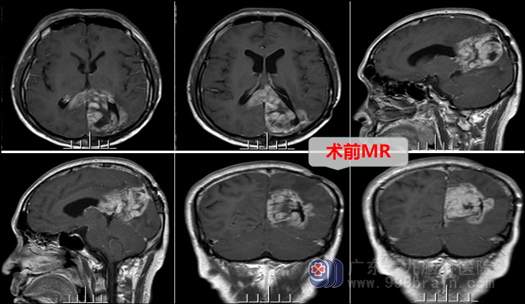

王叔1年前因头晕头痛曾来我院就诊,做了“左侧颞顶枕叶肿瘤切除术”,术后病理报告是:胶质母细胞瘤,即老百姓说的:“脑癌”,因为胶质母细胞瘤为:WHO 4级,脑原发恶性肿瘤,其恶性程度非常高,故当时术后即行同步放化疗,加替莫唑胺辅助化疗,后来恢复较好,回到原籍基本正常生活。但就在近1个月来,王叔又出现了头晕,恶心呕吐的现象,在当地医院复查:“脑肿瘤术后复发”,王叔其实才40岁,是家里顶梁柱,生存愿望非常强烈,但家人非常担忧和着急:这“脑癌”复发了,怎么办?还能再做手术吗?为此,他们再次找到外十科主任欧阳辉教授,欧阳教授看过片子后,明确告诉他们:虽然冒较大风险,但还是可以再为王叔做一次手术。王叔又尽快回到了广东三九脑科医院,找到神经外科欧阳辉团队,主管医生拟“左侧颞顶枕叶胶质母细胞瘤术后复发”收入外十科。

入院后,在完成了各项术前检查和准备工作后,外十科团队于2022年12月6日在全麻下再次行“左侧颞顶枕叶、胼胝体压部、体后部、双侧侧脑室后角旁复发性胶质母细胞瘤切除术”,术中医生在显微镜下耐心细致的切除肿瘤,但还是特别注意保护神经功能和主要血管,手术取得成功。术后当天,病人清醒,四肢活动可,仅有一些头晕头痛等症状,在术后的第三天,王叔已经可以下床活动,言语不流利的症状也在慢慢缓解。